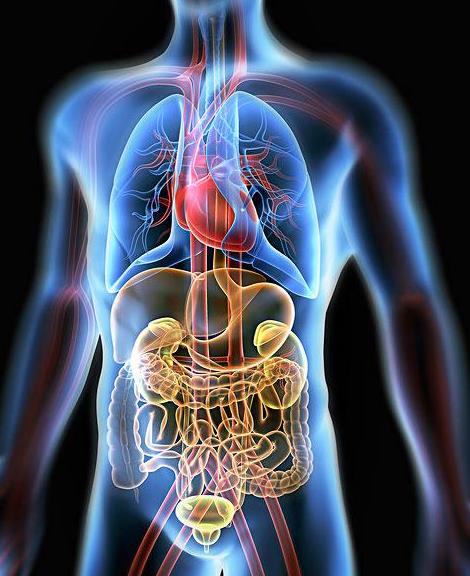

�������Ŀ��ٷ�չ�����ǵ����ʽ��ϰ�߶��õ��˾ߴ�ĸı䣬���а�ҹ�Ӱࡢ����Ӧ�ꡢͨ��������������������ʹԽ��Խ���˵����嶼���뵽���ǽ�����״̬����ν�ǽ��������ǽ��ڼ����뽡��֮�䣬���в������ܾͻἲ����������Ҳ��Ϊʲô���ڵļ�����Խ��Խͻ����ԭ���ڣ�ҽѧר���о����֣�������������ʸ����ԣ��ܹ��к������ڵĻ��������ɻ���ϸ��Ĥ�ϵ�����ɣ����Դ�ϸ���Ƕȵ������壬��ԭ�������������ڻ������Ӷ������彡���������档����7����Ⱥ������Ҫ��ʱ�IJ�����������ӣ���ά�ֽ�����״̬����ô����Щ��������Ҫ�������������أ�

1�����̺Ⱦƣ�æ��Ӧ����� ��̬����������Ѹ���к��̾Ʋ����Ĵ������Զ�����ɻ��ȣ����̾ƶ������Σ��������С�������ܼ��ٶ����̶����ӣ����Ӽ����˵�Σ���������Ժ�ᷢ�־�һ���ȶ�֮��������ѻָ��������ʱ��ȵ��ٶ�һҹ������ʲô�¶��������У�����������������ӣ���ʹ˯һ��֮����Ȼ�����ܡ���һ�㣬�ȾƵ����ѿ����������顣�Ҽ���һ���˿ͣ���ͨ��ͨ�죬������������һ��Сʱ���˾���ȫ���ѣ���ɫҲ�����ˣ�����������Ҳû���κβ������

2�����������ױ��ص��� �������Ӹ���θ�����ڵ����ƽ�⣬3��7�����Ѹ�ٸ��Ʊ���֢״����������������ԭ���Ǹ��������ܹ�������������ϵͳ����ϸ���Ƕ�����

3�����ߡ���Ѫ�ܼ������� ���߶�������ѪҺ�������ӹ��࣬���º�ϸ��ճ����Ѫճ�ȹ��ߣ�ѪҺ���ټ�����ѪҺ��֬�������ѻ�������л����Ѫ�ܺ��������١�����������Ѹ���к������ӣ����ϸ��ճ��������Ѫճ�ȣ�����ϸ���³´�л���ӿ�ѪҺ���٣��Ӷ��ֽ�ʹ�л��ѪҺ�е�֬�����������ѪҺ��������Ѫ�ܡ�

4�������ڰ칫�ң���С���İ�����ϰ�һ�� ���dz�����Ե��ԡ���ӡ�������������ӡ�����綯��������Ȳ����Ĵ������䡢���绷���У�������Ѹ�����ӣ������ӿ��ټ��٣��Խ���Σ���������ӿ����е���̬�������ӣ����������ӣ�������䡢�������������ļ���Σ������ֹ���в�����ͷ�Ρ�ͷʹ�����ꡢʧ�ߵ�֢״�ķ�������߹���Ч�ʡ�

5��������֢�����߷���Ⱥ �����ᶾ���࣬��ʹ�ȵ��ػ����½���Ϊ�����ˡ���Ϊר��ʵ�飺��ҺPHֵÿ�½�0.1����λ���ȵ��ػ��Ծ��½�30%������ϸ�������½�25��26%��������Һ���Թ�ǿ��������������������֢��ͬʱ����֢����ϸ����ת����ɢ�������������к����ڵ��ᶾ���������ƽ�⣬�����ȵ��ػ��ԣ���������������ʣ�����Ѫ���ȶ������Ʋ���֢���������������������ϸ�����ԣ����ư�ϸ��������ת�ƣ�Ԥ�������ķ�����

6����θ���� ���ڳ��������Ƶȴ̼���ʳ�̰ʳ���࣬�����Ĵ����ᶾ����ʴθճĤ��ʹθ������ʧȥƽ�⣬������ʳ������θ�����ᣬ�����±��غ������ӡ�Ӫ���ɷ������ڱ����ɻ���ȥ���Ӷ���������Ϊ�������������ӻ��帺�������������ܳ����к������ᶾ����ԭ��������Ӫ�����ʣ����������������ǿ�������䶯���ܣ������θ���⡣

7������ʧ�ߵ��� ��������ѹ��������ѹ������������ֲ�������ң�����ʧ�ߣ��dz�ʹ�ࡣ�������ӿ��Կ��ٵ������ҵ�ֲ������ѹ���ͽ�����������������ʧ�ߵ����š�

��������������7����Ⱥ������Ҫ��ʱ���������������ģ������ǡ��Ҳ������7����Ⱥ�����Խ��������ӷ��������Խ����������ǻ�Ч����